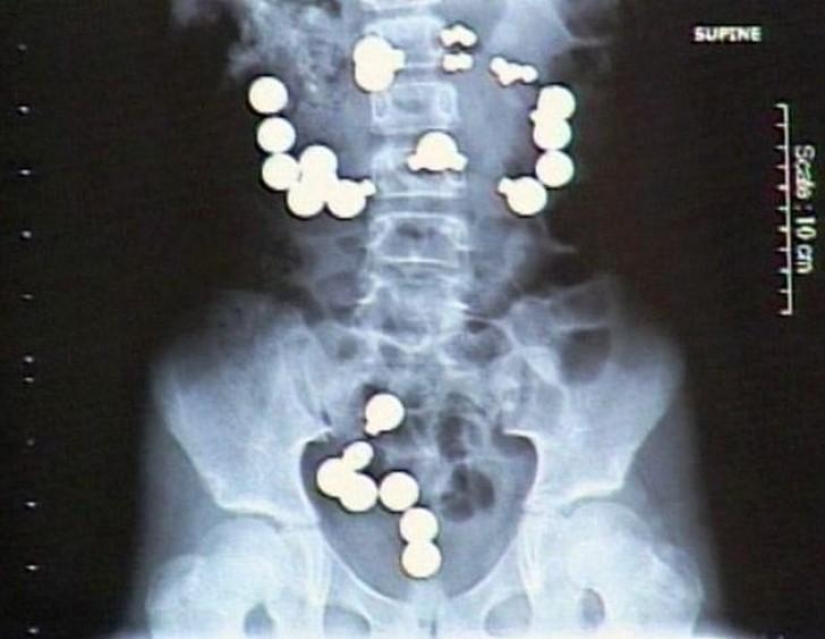

Imanes.